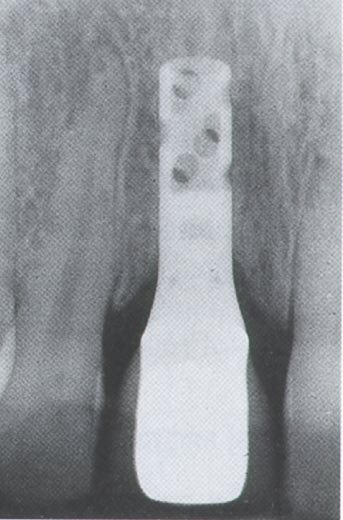

Tissue level implants (some of them hollow cylinder), back then the “ITI system”, were placed in fresh extraction sockets, augmented with GBR and let to heal transmucosally and later be restored with solid abutments. Today I could have considered this impossible, if it wasn’t for a well documented study. The year was 1996, in Bern by Brägger, Hämmerle and Lang. Twenty seven years later, all three were part of the ITI Consensus in Lisbon which accepted A1 immediacy as treatment of choice.

Likewise, the attempt to bring immediacy into the mainstream around 2004 proved to be a bridge too far. The commercial vehicle to materialise the promises of immediacy was soon launched and it was no other than implants designed for placement in extraction sockets aiming to receive immediate provisionals and promising to preserve tissue. Nobel Perfect and Nobel Direct, were two implants launched and marketed as the “immediacy” implants. They were one-piece implants with certain features that were expected to optimise outcomes of placement in fresh extraction sockets. Among these was the provision for a cement retained crown, the lack of an implant-abutment “gap” and also the coronal extension of rough surface, which was envisioned to enhance the attachment of the soft tissue. For this purpose and also to support interproximal papilla, Nobel Perfect had scalloped margins of the rough surface. The spatial positioning of an immediate implant at that time was also not perceived as today; there was a misguided view that filling the socket with titanium was the element which lead to bone preservation. This might be the principle behind another immediacy implant, around that time from Straumann, the TE implant which was a tissue level implant with characteristically wider coronal part.